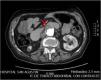

Varón de 83 años con antecedente de leucemia linfoide crónica estadio inicial (0 de Rai/A de Binet), que ingresó por náuseas, vómitos y estreñimiento de varios días de evolución. Se realizó una TC abdominal en la que se observa un engrosamiento de las paredes de la 3.ª-4.ª porción duodenal, así como un gran aneurisma aórtico que comprime el duodeno de forma extrínseca (fig. 1). En una gastroduodenoscopia se observó una estenosis ulcerada prácticamente completa de la 3.ª porción duodenal (figs. 2 y 3). La biopsia mostró una infiltración de la mucosa duodenal por células grandes de estirpe linfoide, escasamente cohesivas y con escaso citoplasma, CD 20+ y CD 3– (fig. 4), compatible con linfoma B de células grandes. El síndrome de Richter aparece en el 2-10% de los pacientes con leucemia linfoide crónica, y consiste en su transformación en un linfoma agresivo, en la mayoría de los casos un linfoma B difuso de células grandes. Generalmente se manifiesta con adenopatías, esplenomegalia y empeoramiento de síntomas B. Nuestro paciente comenzó con un cuadro suboclusivo, iniciándose tratamiento quimioterápico. Recibió 3 ciclos (2 R-miniCHOP y R-Gem-Ox-Dexa) sin mejoría, siendo finalmente intervenido mediante gastroyeyunostomía laparoscópica. La evolución fue desfavorable, presentando en las semanas posteriores un abdomen agudo, secundario a isquemia mesentérica extensa, siendo intervenido de nuevo, pero falleciendo en el postoperatorio.